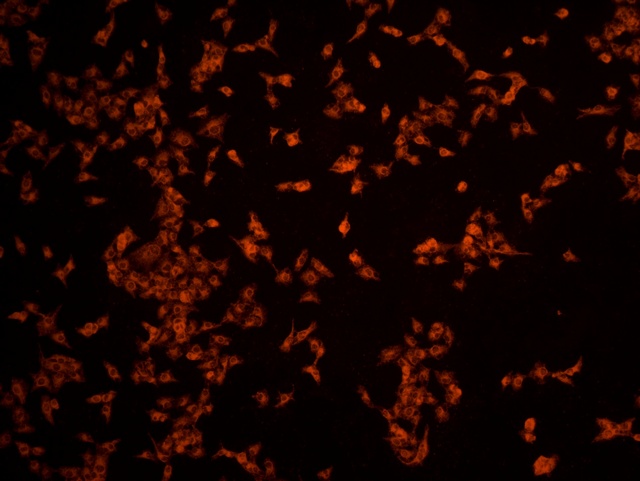

南華大學在生物醫學研究領域一直走在學術前沿,近日,該校引進Mshot明美的倒置熒光顯微鏡MF52-N,搭配顯微鏡相機MSX2,為細胞切片標本的研究提供了強大的技術支持,進一步提升了科研實力。

MF52-N倒置熒光顯微鏡以其數顯LED熒光模塊和深度優化的光路設計,成為細胞切片觀察的理想選擇。其簡單易用的熒光激發操作,大大降低了實驗難度,提升了工作效率。同時,該顯微鏡還能提供高質量的相襯、熒光和明場成像,確保科研人員能夠捕捉到細胞切片的每一個細節。

在南華大學的實驗室中,科研人員正借助這套先進的顯微系統,對細胞切片標本進行深入探索。

此外,MSX2顯微鏡相機的加入,更是如虎添翼。這款相機以其高分辨率和敏銳的圖像捕捉能力,記錄了實驗過程中的每一個重要瞬間,為數據分析與論文發表提供了有力支持。